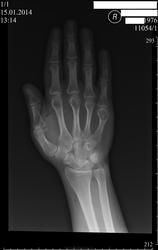

Пациент 37 лет. Приблизительно  5 лет  тому назад заметил увеличение в объёме области головки V пястной кости, боль при рукопожатии. Ваше мнение и какова может быть дальнейшая тактика?

Думаю, энхондрома. Мы в таких случаях направляемя на консультацию к онкологу.

Я написал в заключении больше данных за энхондрому. Порекомендовал консультацию ортопеда(  предварительно звонил онкологу и он скзал, что такой нозологией у нас ( в регионе) занимаются ортопеды).

+1 за энхондрому

энхондрома,занимается ортопед

А, это костной кистой не может быть?

Плотновато для дырки будет. И это не по моему мнению, как говорил уважаемый коллега, - скиалогия здесь не та.

Сложно бывает различть энходрому, кисту и гигантоклеточную опухоль. Но тут, я думаю, ближе к энхондроме. Содержимое выглядит неоднородным, с включениями. Одним словом, гистология покажет.

Да, но содержимое это слишком на много частей в ней будто бы разделено. Многокамерная киста? Может так. Но нет ободка-контура для кисты, зато есть костно-хрящевая ткань. Пусть и по-моему, но как-то так.)